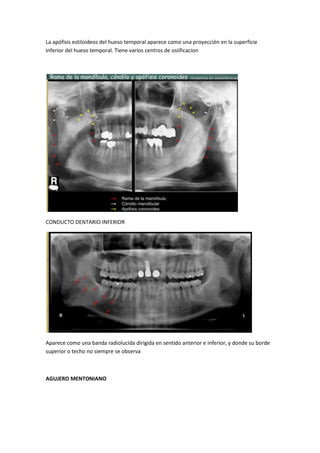

La apófisis estiloideos del hueso temporal aparece como una proyección en la superficie

inferior del hueso temporal. Tiene varios centros de osiificacion

CONDUCTO DENTARIO INFERIOR

Aparece como una banda radiolucida dirigida en sentido anterior e inferior, y donde su borde

superior o techo no siempre se observa

AGUJERO MENTONIANO